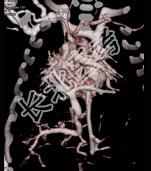

- 多项选择题女性,21岁, 活动后呼吸困难,时常发生上呼吸道感染, CT扫描如图所示,请选择正确的选项 ( )

A、考虑为肺静脉异位引流

D、该病人肺静脉异位引流入下腔静脉

E、该病人为心下型肺静脉异位引流